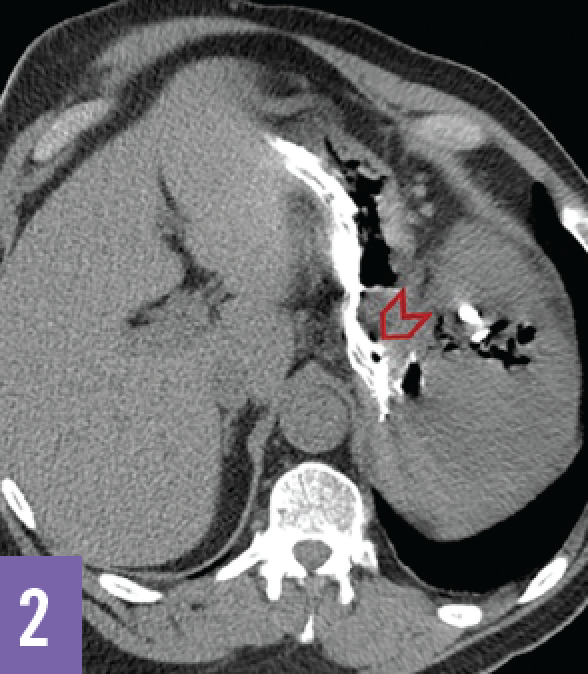

Arielle Gire-Dumas, MD; Mamta Parikh, MD; Jeremy DiMartini, MD; Paul Aronowitz, MD

A 62-year-old man with a history of stage 5 chronic kidney disease, type 2 diabetes mellitus, gout, and hypertension presented to the emergency department after having run out of peritoneal dialysate...